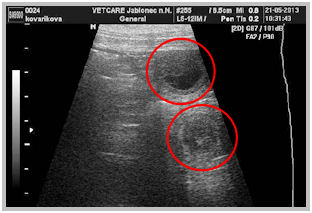

21.5.13 Dnes jsem byla s Atynkou na ultrazvuku. Na fotkách jsem viděla 5 nádherných kuliček, 3 vlevo a 2 vpravo. Paní doktorka Aty vyholila jen malý kousek chlupů na bříšku a tak jsme možná všechna štěnda neviděly a nějaké bude ještě někde schované. Výsledný počet bude překvapení a uvidíme co nám Atynka nadělí.

Na fotkách níže vidíte naše miminka a na spodních fotkách, jak asi nyní vypadají.

border collie speedy dream border collie speedy dream

border collie speedy dreamborder collie speedy dream